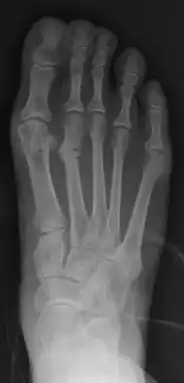

Primus varus deformity

Primus varus deformity is the leaning of the first metatarsal bone away from the second metatarsal and towards the opposite foot (Fig. 1). As it leans over, its head sticks out to form the bunion bump and it also widens the forefoot to cause shoes feeling too tight. Thus when bunion pain becomes unmanageable, surgical correction is to narrow the forefoot by repositioning of the first metatarsal head back to its normal position. This can be done by osteotomy (bone-breaking), soft tissue (non-osteotomy) or fusion techniques.